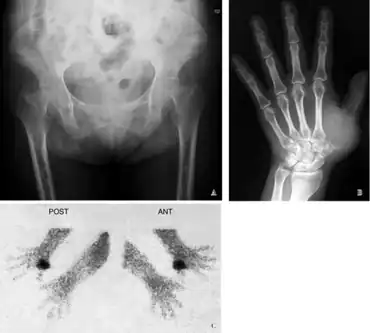

Radiographic characteristics

Radiological appearances include:

- Pseudofractures, also called Looser's zones.

- Protrusio acetabuli, a hip joint disorder

Furthermore, a technetium bone scan will show increased activity (also due to increased osteoblasts).